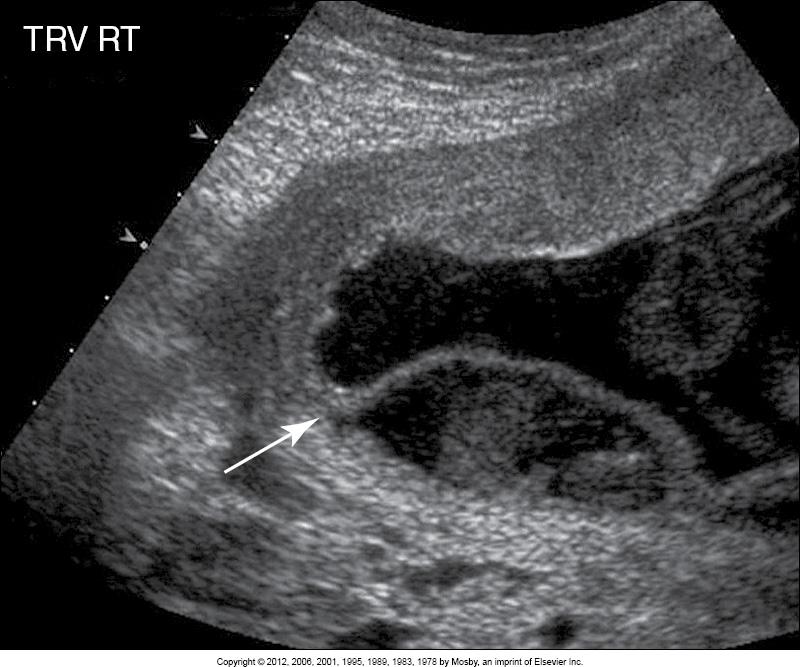

What does the arrow point to?

circumvallate/circummarginate placenta